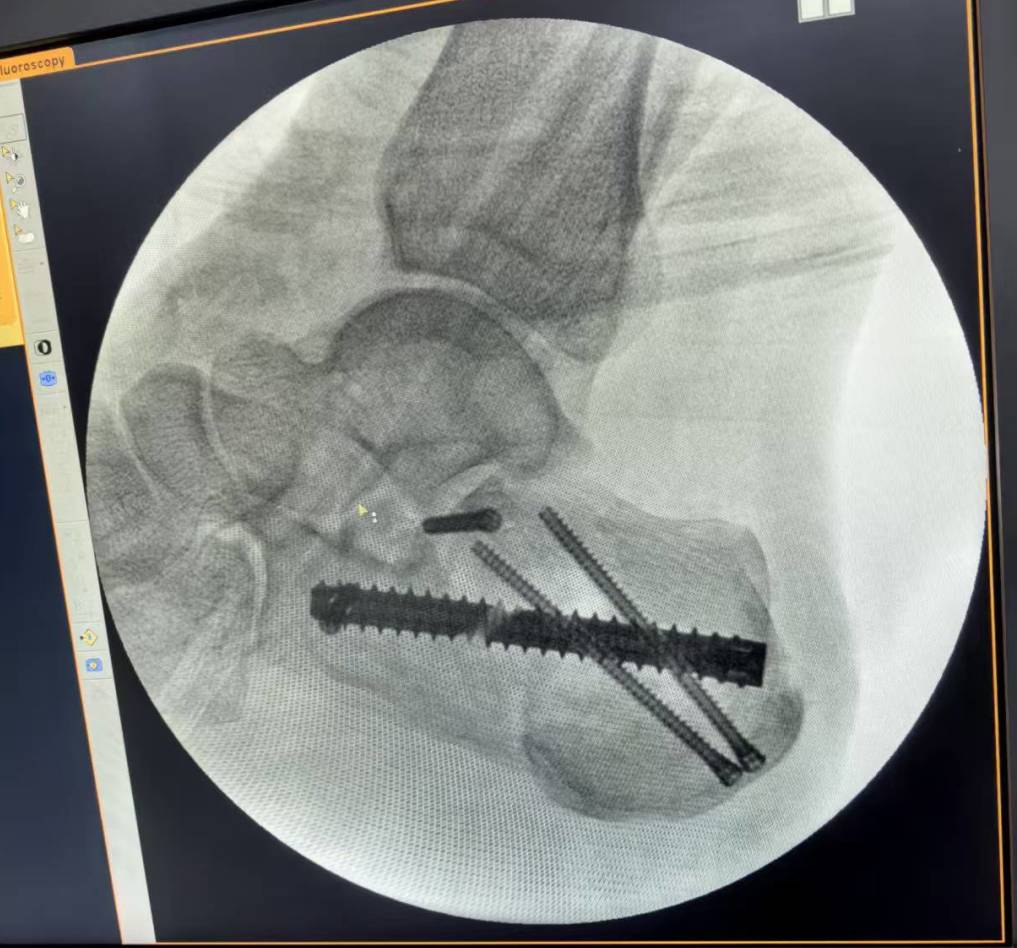

术后影像

本次手术邀请山大二院手足外科专家李政勋主任现场指导,骨三科医师团队明确分工,精细操作,采用关节镜辅助技术,于微创视野下清晰探查跟骨后关节面的粉碎性骨折情况,精准清理增生滑膜、游离体及凝血块,借助钉中钉内固定系统实现骨折块的稳定复位与固定。该术式具有创伤小、出血少、复位精准、恢复快等优势,最大程度减少了对周围软组织的损伤,降低了术后并发症风险,为患者快速康复奠定了坚实基础。手术历时2个多小时成功完成。术后患者恢复顺利,目前正处于积极康复中。